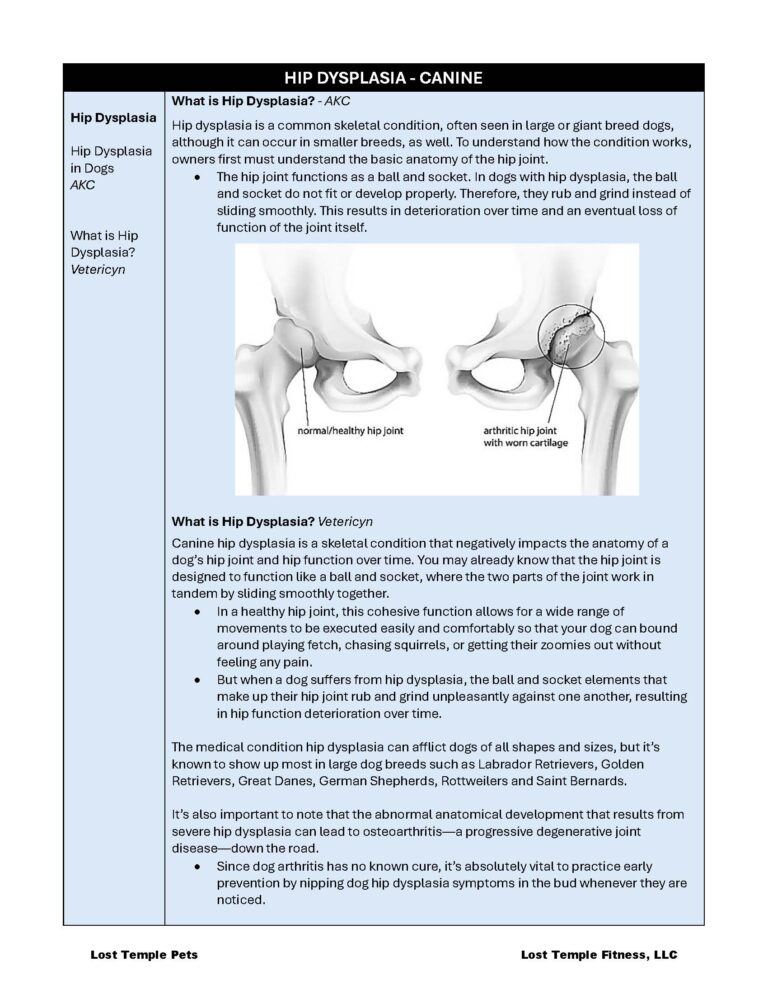

Hip dysplasia is a common skeletal condition, often seen in large or giant breed dogs, although it can occur in smaller breeds, as well. To understand how the condition works, owners first must understand the basic anatomy of the hip joint.

- The hip joint functions as a ball and socket. In dogs with hip dysplasia, the ball and socket do not fit or develop properly. Therefore, they rub and grind instead of sliding smoothly. This results in deterioration over time and an eventual loss of function of the joint itself.

Canine hip dysplasia is a skeletal condition that negatively impacts the anatomy of a dog’s hip joint and hip function over time. You may already know that the hip joint is designed to function like a ball and socket, where the two parts of the joint work in tandem by sliding smoothly together.

- In a healthy hip joint, this cohesive function allows for a wide range of movements to be executed easily and comfortably so that your dog can bound around playing fetch, chasing squirrels, or getting their zoomies out without feeling any pain.

- But when a dog suffers from hip dysplasia, the ball and socket elements that make up their hip joint rub and grind unpleasantly against one another, resulting in hip function deterioration over time.